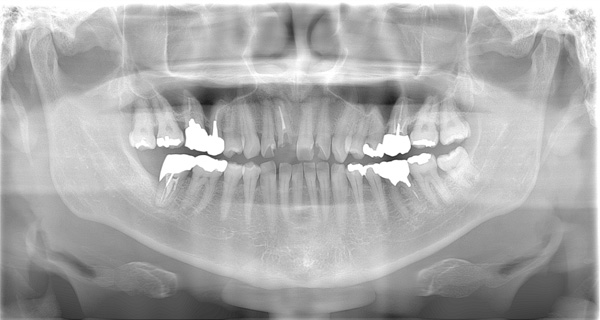

| 年代・性別 | 50代 男性 |

|---|---|

| 主訴 | 右上下の歯が痛い |

| 治療期間 | 約12ヶ月 |

| 費用 | 2,500,000円 |

| 治療内容 | インプラント、骨造成、結合組織移植、セラミック修復 |

| 治療に伴うリスク | インプラント周囲炎 セラミックの破折、脱離 |

*キャンセルポリシーをご一読のうえご予約ください